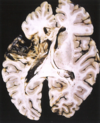

# Alzheimer

Atrofia difusa Estrechamiento de las circunvoluciones Ensanchamiento de los surcos Hidrocefalia ex vacuo (no se ve) - dilatación ventricular compensadora

Figura 28.36 Enfermedad de **Alzheimer** con atrofia cortical más notoria en la derecha, donde se han extirpado las meninges.